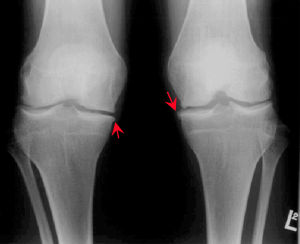

X線檢查:正位片顯示關節間隙變窄,關節邊緣硬化,有不同程度的骨刺形成。

最常發生的部位應該是膝關節。膝關節承受了人體的大部分的重量,而且位置淺,活動量大,特別是在活動過程中由於關節不穩,容易引起損傷。另外一個原因是由於中老年人的內分泌系統功能減弱,關節營養來源的的滑液分泌隨之減少,容易出現骨質疏鬆,關節軟骨變軟變薄,承壓能力減低,關節軟骨磨損加劇,於是關節軟骨面出現反應性增生,形成骨刺。

當骨刺增長到自身不能調節的時候,骨刺周圍的軟組織就會充血、水腫、炎症、粘連、壓迫神經及血管,引起一系列的臨床病症,如軟骨凹凸不平、關節縫隙狹窄、軟骨磨損缺失,這就是關節退行性變。